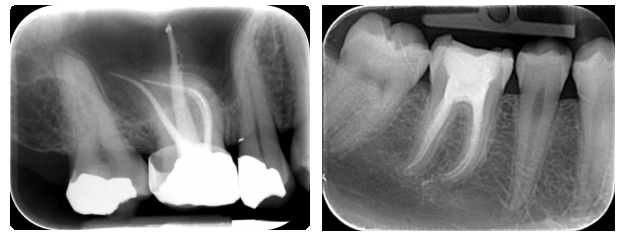

In some cases the differences in diagnoses do not allow the treatment to be complete in one visit i.e. we need to put the patient on medicine for some period. Endodontics is when the caries lesion has advanced so much that it has extended even to the tooth pulp, so it needs appropriate treatment depending on the specific diagnosis. When the infection is located only to the tooth pulp we are speaking about pulpitis. In the case when there is gangrenous decomposition of the pulp, with the releasing of gasses of anaerobic bacteria, than that’s gangrene. When the inflammation process has gotten to the periodontium through the root canals than that’s periodonitis?.

Endodontic treatment involves opening the tooth, removing the damaged pulp, cleaning, shaping, filling and sealing the tooth. For successful treatment we use quality antiseptic solutions, medicine for temporary and permanent sealing of the root canals based on calcium hydroxide. We also use nickel titanium endodontic instruments that put the risk of treatment failure to a minimum, which was a serious problem in the past.